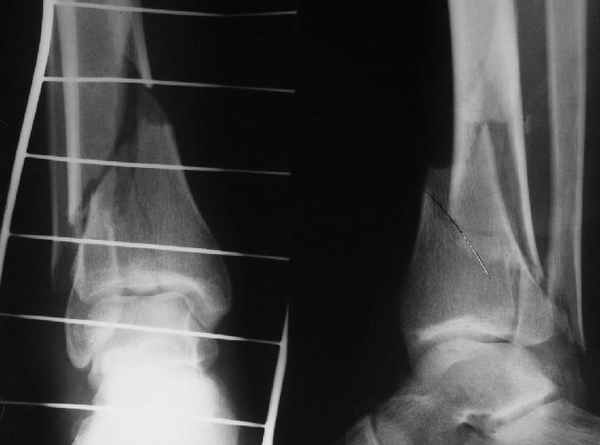

Да и нет! Зависит от перелома и способа остеосинтеза. А результат? (01)

А в данном случае - у нас был бы применен locked nail с еще меньшими дырочками на коже и с возможностью полной нагрузки немедленно после операции. Какие тут аргументы в пользу выбора пластины, а не интрамедуллярного гвоздя?

Аргументы: перелом достаточно низкий, трудно будет ввести 3-и блок. винта, а учитывая характер перелома на 2-х дистальных винтах я бы не рекомендовал немедленную полную нагрузку.